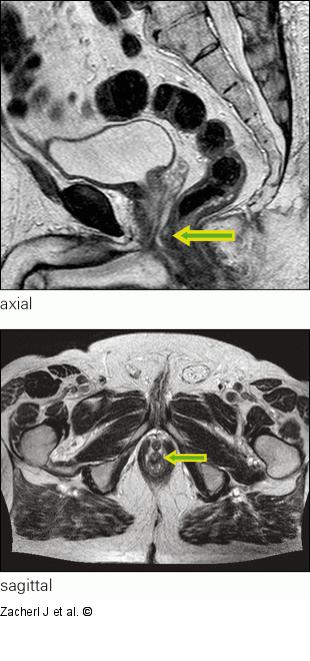

Abbildung 4: Submukosaler Tumor MRT axial und sagittal 11/2012 (T2-Gewichtung) |

Abbildung 4: Submukosaler Tumor

MRT axial und sagittal 11/2012 (T2-Gewichtung) |